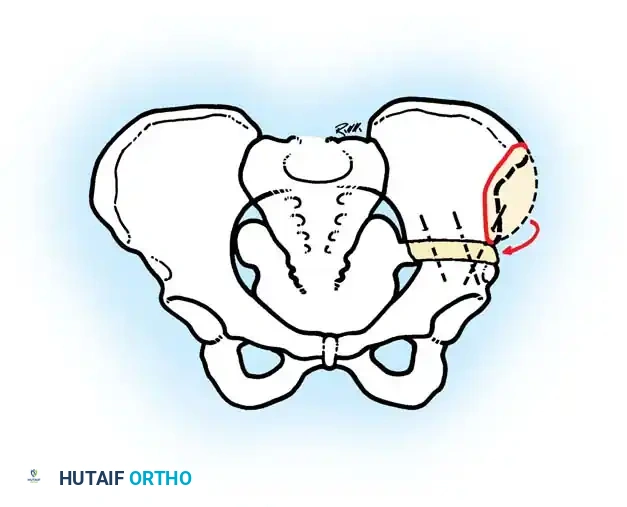

Surgical Management: Pelvic Osteotomies

Innominate osteotomies, such as the Salter osteotomy, provide containment by redirecting the acetabulum to cover the anterolateral aspect of the femoral head without altering the proximal femoral anatomy. This is particularly advantageous in older children where remodeling of a varus femur is less predictable, or in cases where limb shortening is undesirable.

Salter Innominate Osteotomy Technique:

1. Approach: A Smith-Petersen (anterior) approach is utilized. The interval between the tensor fasciae latae and the sartorius is developed.

2. Exposure: The iliac apophysis is split, and the inner and outer tables of the ilium are stripped subperiosteally down to the greater sciatic notch.

3. Osteotomy: A Gigli saw is passed through the sciatic notch and directed anteriorly to exit at the anterior inferior iliac spine (AIIS).

4. Redirection: The distal acetabular fragment is hinged on the pubic symphysis and rotated anterolaterally, pivoting on the triradiate cartilage.

5. Grafting and Fixation: A triangular wedge of bone (harvested from the anterior iliac crest) is impacted into the osteotomy gap. The construct is stabilized with two or three threaded Kirschner wires driven from the proximal ilium, through the graft, and into the distal fragment.